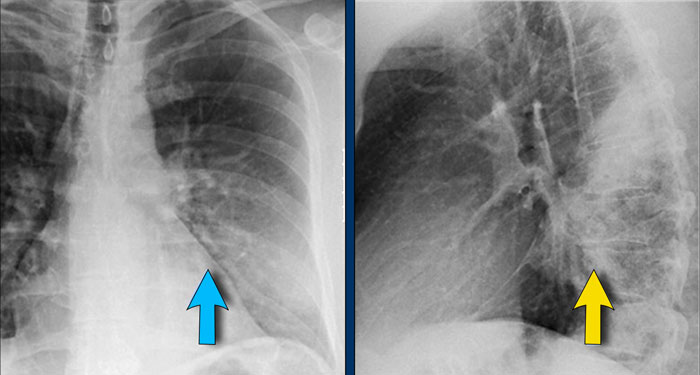

1. No silhouette sign in a consolidation located in the left lower lobe (blue arrow). 2. Silhouette sign in a consolidation in the lingula lobe (yellow arrow). 1. No silhouette sign in a consolidation located in the left lower lobe (blue arrow). 2. Silhouette sign in a consolidation in the lingula lobe (yellow arrow).

Silhouette sign

The silhouette sign refers to the loss of the normal border between structures of different radiographic densities, most commonly air-filled lung adjacent to soft tissue structures like the heart or diaphragm.

This sign is crucial for detecting subtle pathology and localizing lesions within the thorax.

Illustration of the Silhouette Sign

1. No Silhouette Sign (Blue Arrow)

• The left ventricle, located anteriorly, is normally bordered by air-filled lingula of the left upper lobe.

• If a consolidation occurs in the left lower lobe (posterior), the interface between the lingula and the heart remains intact, and the left heart border is preserved.

2. Positive Silhouette Sign (Yellow Arrow)

• When consolidation is present in the lingula, which directly abuts the left heart border, the silhouette of the left ventricle becomes obscured.

• This indicates the pathology is located anteriorly in the chest.

Silhouette Sign – Examples

Case 1: PA View

• The left heart border is obscured on the PA radiograph.

• Without even reviewing the lateral view, this finding localizes the pathology to the anterior segment of the left lung, likely the lingula.

• Diagnosis: Lobar pneumonia due to Streptococcus pneumoniae.

Case 2: PA View

• A consolidation is visible in the left lower lobe (yellow arrow).

• The left heart border remains well-defined with a normal silhouette (blue arrow), indicating the lesion is posterior, not involving the lingula.